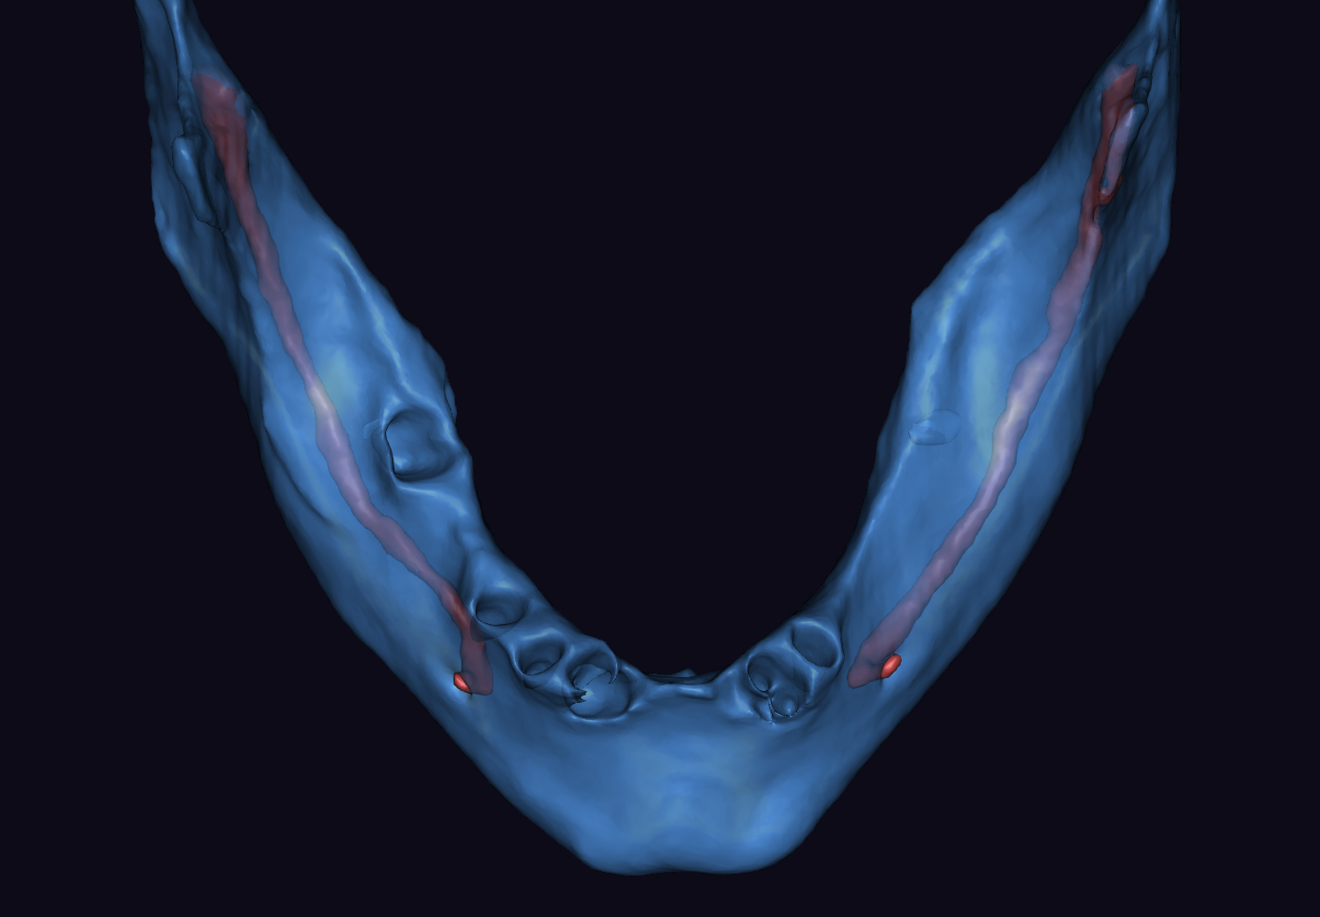

Figs. 2a & b: Intra-oral scans of the pre-op situation.

Fig. 2b